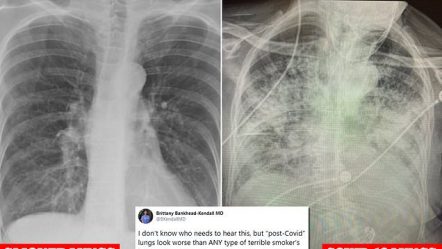

Dy të tretat e rusëve besojnë se Covid-19 është një armë biologjike, zbulon anketimi (fotot)